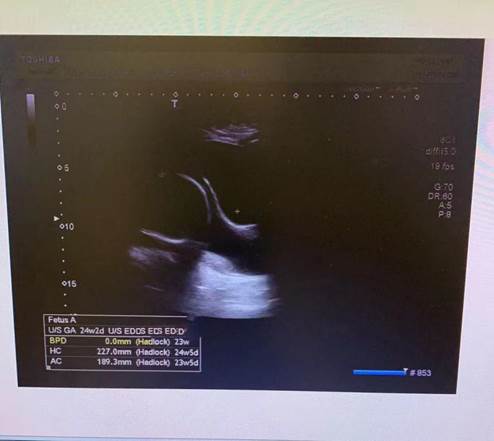

患者小高,孕24周,因“阴道分泌物略多”来院就诊,偶感下腹坠胀,B超提示:宫颈口喇叭状,宫颈内口见有25*28mm液性暗区。阴道检查:宫颈质软,开大2cm,宫颈内口羊膜囊感明显。

B超配图